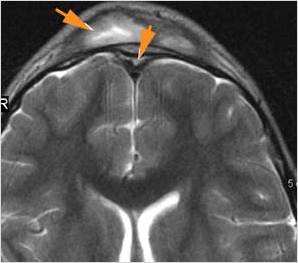

There is a subdural fluid collection or abscess along the boney walls of the anterior or middle cranial fossa. [Yes/No]

There is a subdural fluid collection or abscess along the falx cerebri or within the tentorium. [Yes/No]

There is evidence of thrombus, thrombophlebitis or other occlusive or inflammatory process of the cortical veins, sphenoparietal sinus or sagittal sinus. [Yes/No]